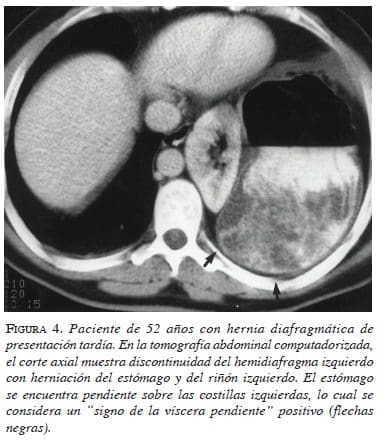

Se ha descrito el llamado “signo de la víscera pendiente”, que se produce porque los pacientes se encuentran en posición supina cuando se toma la TC; cuando el diafragma está roto, las vísceras herniadas pierden el soporte posterior que les brinda el diafragma y caen a una posición “pendiente”, apoyándose sobre las costillas posteriores. Al lado derecho, habitualmente el tercio superior del hígado no se encuentra apoyado contra la pared posterior del tórax cuando el diafragma se encuentra intacto. Al lado izquierdo, el estómago y el intestino generalmente no se apoyan en las costillas de la pared izquierda del tórax cuando el diafragma se encuentra intacto, y el estómago o intestino no se encuentran posteriores al bazo. Consecuentemente, el signo de la víscera pendiente se encuentra presente en el lado derecho cuando el tercio superior del hígado se apoya contra las costillas derechas y, en el lado izquierdo, cuando el estómago o los intestinos se apoyan sobre las costillas izquierdas a la altura de la décima vértebra torácica. La tasa de diagnóstico mediante la aplicación de este signo radiológico, se ha incrementado a 90 % o más, con un valor diagnóstico de 1. Este signo se observa en el 100 % de los casos con lesión del diafragma izquierdo y en 83 % de los pacientes con lesiones derechas20,21 (figuras 4 y 5). Los cortes sagitales y coronales en las reconstrucciones de la TC de múltiple corte, permiten observar el estómago o los intestinos herniados dentro del tórax, como se observa en la figura 6.